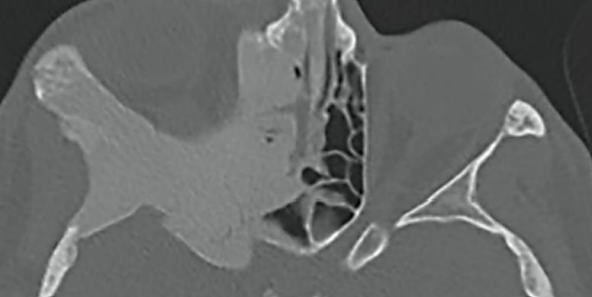

A estrutura apontada pela seta corresponde a:

A imagem a seguir corresponde mais provavelmente a: